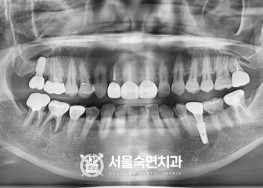

임플란트-치료-전후사진

서울대학교-출신-보건복지부-인증-통합치의학과-전문의-2인-책임관리